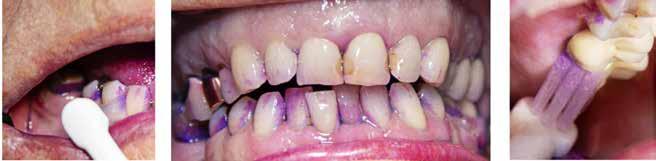

Nonoperativ cariesbehandling

Fig. 8. En delvist frembrudt mandibulær 3. molar, som viser et okklusalt aktivt læsionsmiljø, inden afpudsning (”baseline”) samt under en 3-ugers sekvens af professionel biofilmfjernelse (”1 week”, ”2 week”, ”3 week”). Der ses status før bakteriel indfarvning (venstre kolonne), efter bakteriel indfarvning midterkolonne og efter professionel fjernelse af den farvede biofilm (højre kolonne). Aktive emaljelæsioner bemærkes koronalt på begge sider af fure-fossa-systemet. Der ses også en carieslæsion på facialfladen cervikalt. Efter både professionel fjernelse og individuel instruktion reduceres laget af biofilm (hvid pil, nederste række, ”3 week”) sammenlignet med ”baseline” (hvid pil, øverste række).

Derudover har emaljelæsionerne påbegyndt en misfarvning centralt (sorte pile, ”2 week,” ”3 week”), hvilket fortolkes som tegn på standsede læsioner/langsomt progredierende læsioner. (©Lars Bjørndal 2022).